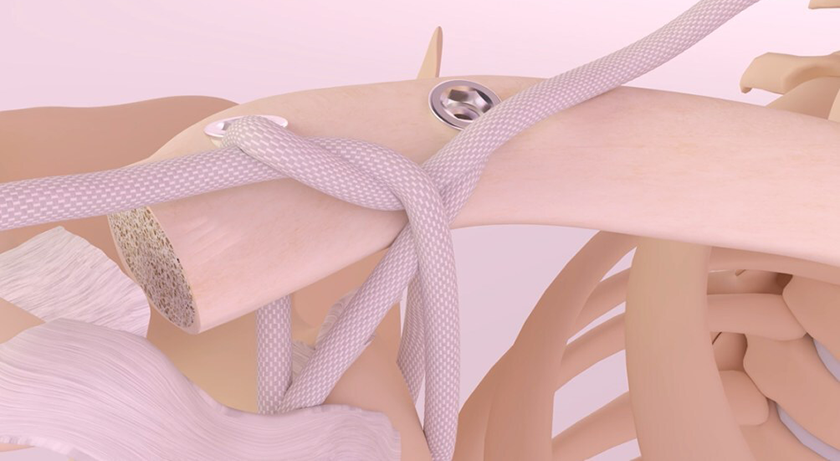

Active Implants’ NUsurface meniscus is intended to treat patients with persistent knee pain following medial meniscus surgery. As a result of its unique medical-grade polymer, composite structure and design, it does not require fixation to bone or soft tissues. The implant mimics the function of the natural meniscus and redistributes loads transmitted across the knee joint. NUsurface is available in Belgium, Germany, Italy and Israel and received FDA Breakthrough Designation in September of 2019. The company seeks clearance in early 2021 as it works with FDA through the De Novo review process.

NovoPedics’ MeniscoFix is a polymer fiber-reinforced scaffold for total meniscus replacement designed to be gradually resorbed by the body and replaced by new tissue. Its fiber-reinforced design is similar to the native meniscus. The device is attached to both soft tissue and bone. In contrast to partial meniscus replacement devices, MeniscoFix is uniquely designed to be securely fixed within bone tunnels and to support mechanical loads along the entire implant, making it potentially useful even in patients with a compromised meniscal rim. It was granted Breakthrough designation in September 2020. NovoPedics received a $4.42 million grant from the U.S. Department of Defense to support further pre-clinical development at Rutgers University.

Orteq’s ACTIfit offers a unique alternative to partial meniscectomy. The biodegradable scaffold is the result of polymer science and tissue regeneration technology developed in the Netherlands. ACTIfit’s polymer is a biodegradable polyurethane and is processed by solvent casting/porogen leaching to create a porous scaffold. ACTIfit is approved under the European CE Mark and in Korea and was granted FDA Breakthrough designation in April of 2020. Orteq is taking steps toward FDA 510(k) clearance. Though it is uncertain how soon the ACTIfit could be cleared for commercialization in the U.S., Orteq hopes that its extensive body of scientific and clinical evidence from Europe will support a timely approval.